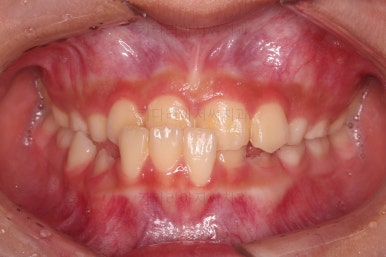

Case 1. 전/후

CASE 1.

나이 : 9세

총 치료기간 : 3개월

바로 전후 비교사진 올립니다.

골격의 문제가 없었고 골격에 대한 치료가 아니었지만 얼굴 모습도 약간의변화가 있죠?

함몰감이 약간 있던 윗입술 부분이 볼륨감이 생기면서 자연스러운 아이얼굴 비율이 되었어요.

치열도 자연스럽게 예뻐졌네요.

3개월만에요😄